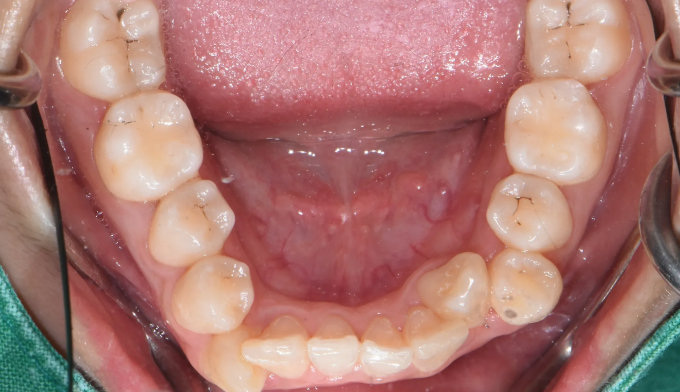

Before

아래치아도 갯수를 맞춰주기위해 하나씩 발치하였습니다.